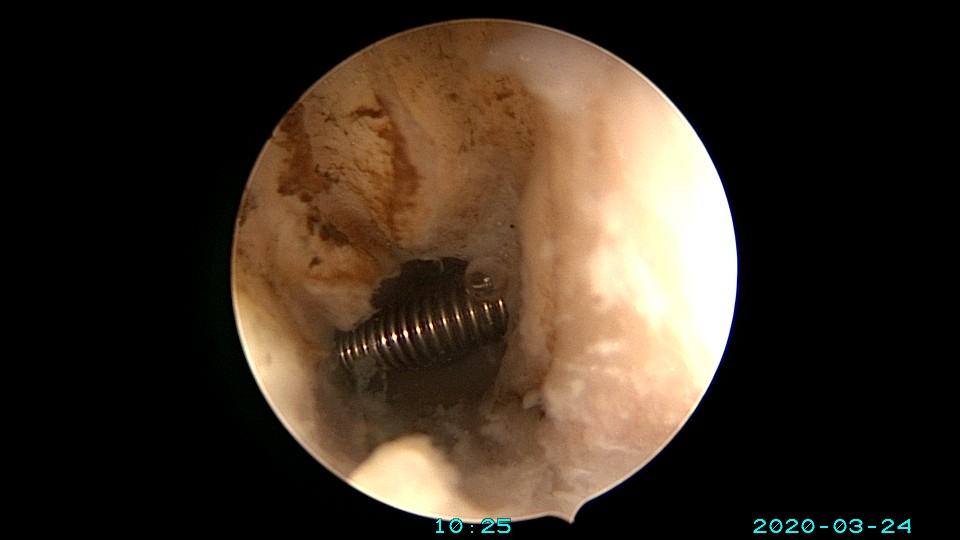

患者65岁,G1P1,顺产1次。安环30年,绝经10年。外阴白斑,阴道明显萎缩,无法置入扩阴器,阴道内镜方式找到宫颈外口,宫颈萎缩,穹隆几乎消失,无法夹持宫颈,宫颈管见多个息肉,宫颈内口狭窄坚硬,难以扩张。微型异物钳探查宫腔方向,用异物钳、微型剪刀扩大宫颈内口失败,改用双极电针切开宫颈内口,但镜子仍无法进入宫腔。用异物钳反复牵拉O型环至阴道内,中弯钳配合卵圆钳拉出节育环,环变形。有人问我何不用取环钩取环,这个病人探针和取环钩都无法发挥作用。